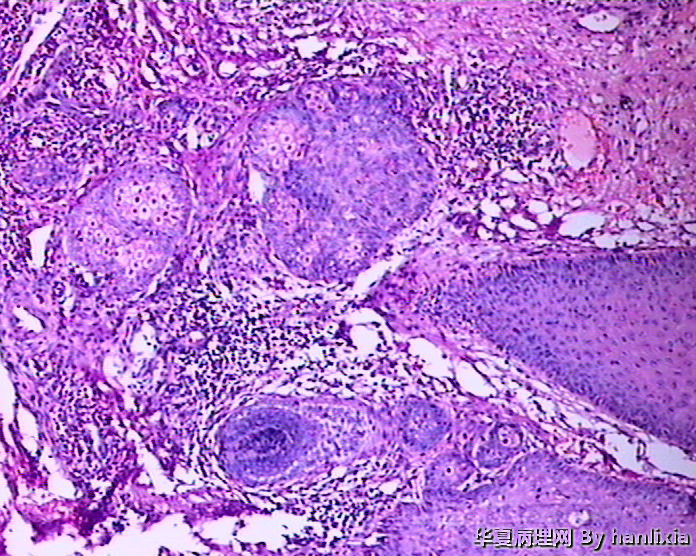

男性患者,50岁,发现面部皮肤(耳旁)肿物一年余,色黑。

高分化鳞状细胞癌

高分化鳞癌可能,也可能AK基础上发展而来的浅表型鳞癌?

部分区域突破基底膜,应该诊断鳞癌,由日光性角化发展过来的!